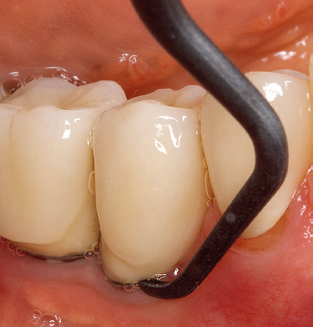

Unerlässlich für die UPT implantat prothetisch versorgter Patienten sind natürlich Arbeitsspitzen für die Reinigung von Implantatoberflächen. Der Implantatreinigungsaufsatz des hier verwendeten Systems zeichnet sich dabei durch eine spitz zulaufende sechskantige konische Form aus. Dieses Design erlaubt ein leichtes atraumatisches Eindringen in die periimplantäre Tasche und zeigt eine gute Reinigungsleistung (Abb. 7).